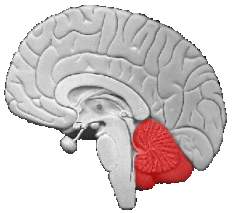

Il cervelletto è chiamato così perché sembra un piccolo cervello. Sta “nascosto” dietro e sotto al cervello ed è attaccato al tronco encefalico. Se volete posizionarlo nella vostra immaginazione è dove sta la nuca. Il suo preciso funzionamento è costantemente sotto indagine, come tutto d’altronde. Pensate che è difficile anche descriverlo anatomicamente. Infatti ci sono decine di nomenclature.

Il cervelletto è “sbocciato” dai nuclei vestibolari. Ripercorrendo le funzioni dei vestiboli e delle sue centraline (nuclei) e possiamo intuire il ruolo del cervelletto nelle sue funzioni basilari. Il cervelletto inoltre ha un ruolo importante nella cognizione e nelle funzioni cerebrali superiori (la parola, le emozioni, il pensiero astratto ecc).

Con l’evoluzione che ci ha portato appendici sotto forma di arti, questo sistema vestibolo-oculo-spinale, ha avuto bisogno di maggiori strutture per gestire gli arti, la prensilità delle mani e la deambulazione bipodalica. Quindi, piano piano nell’evoluzione della complessità delle forme di vita è sbocciato il cervelletto. Sembra che sia stata la crescita del cervelletto a guidare la formazione del cervello. Anche se poi noi lo abbiamo chiamato il piccolo cervello! Da questo modello, possiamo intuire il ruolo del cervelletto anche per gli aspetti cognitivi superiori che normalmente ascriviamo agli emisferi cerebrali.

Il cervelletto si integra con tutte le funzioni vestibolari e riceve le informazioni da tutte le articolazioni del corpo e da tutti i muscoli e tendini.